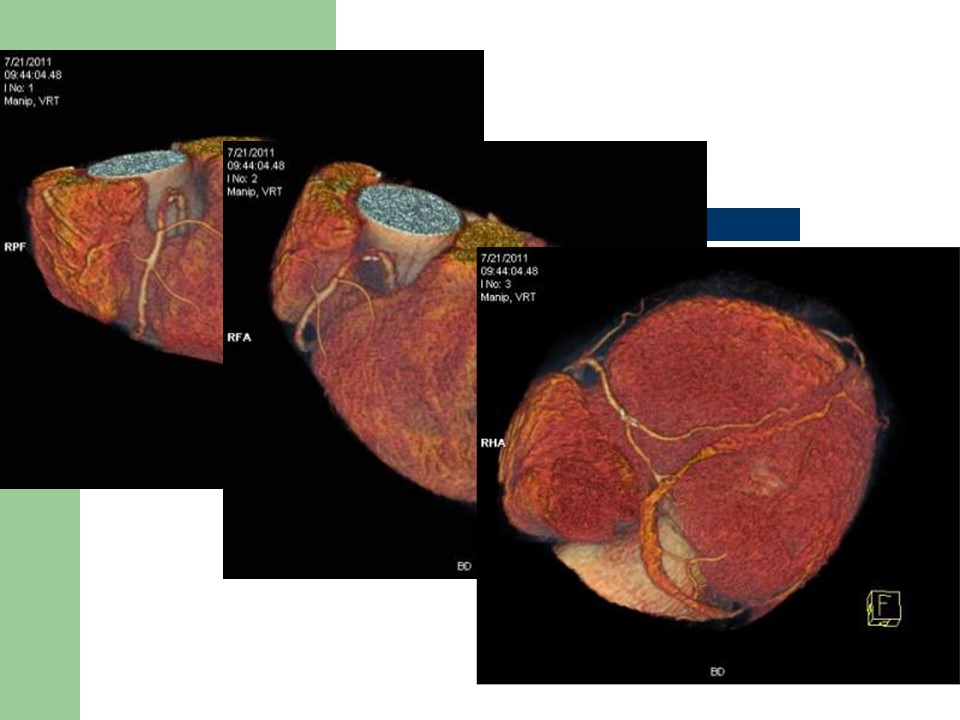

“冠状动脉常见疾病的双源CT表现” 的相关文章